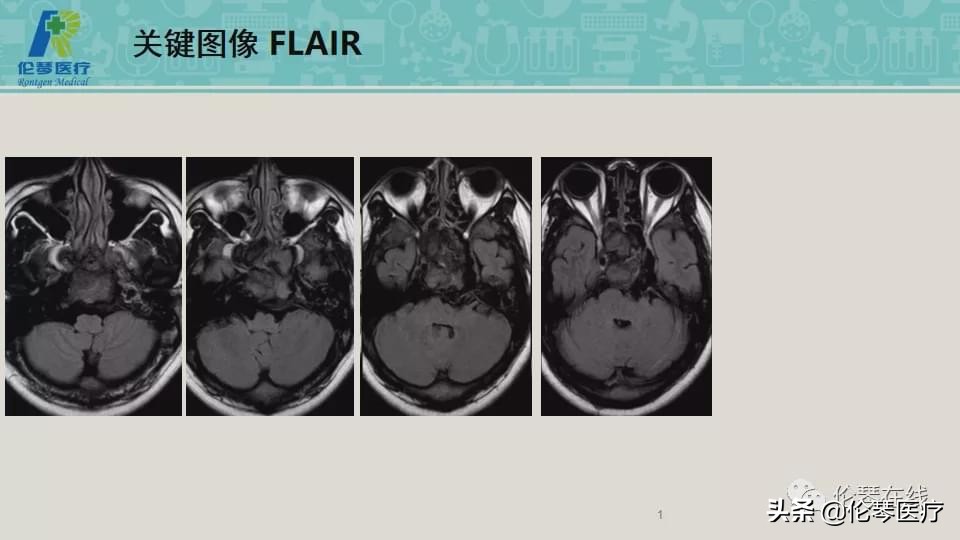

性别:男

年龄:21岁

主诉:头痛,双眼内收、外展受限8个月,加重2月

检查:CT扫描(影像图像见下方)